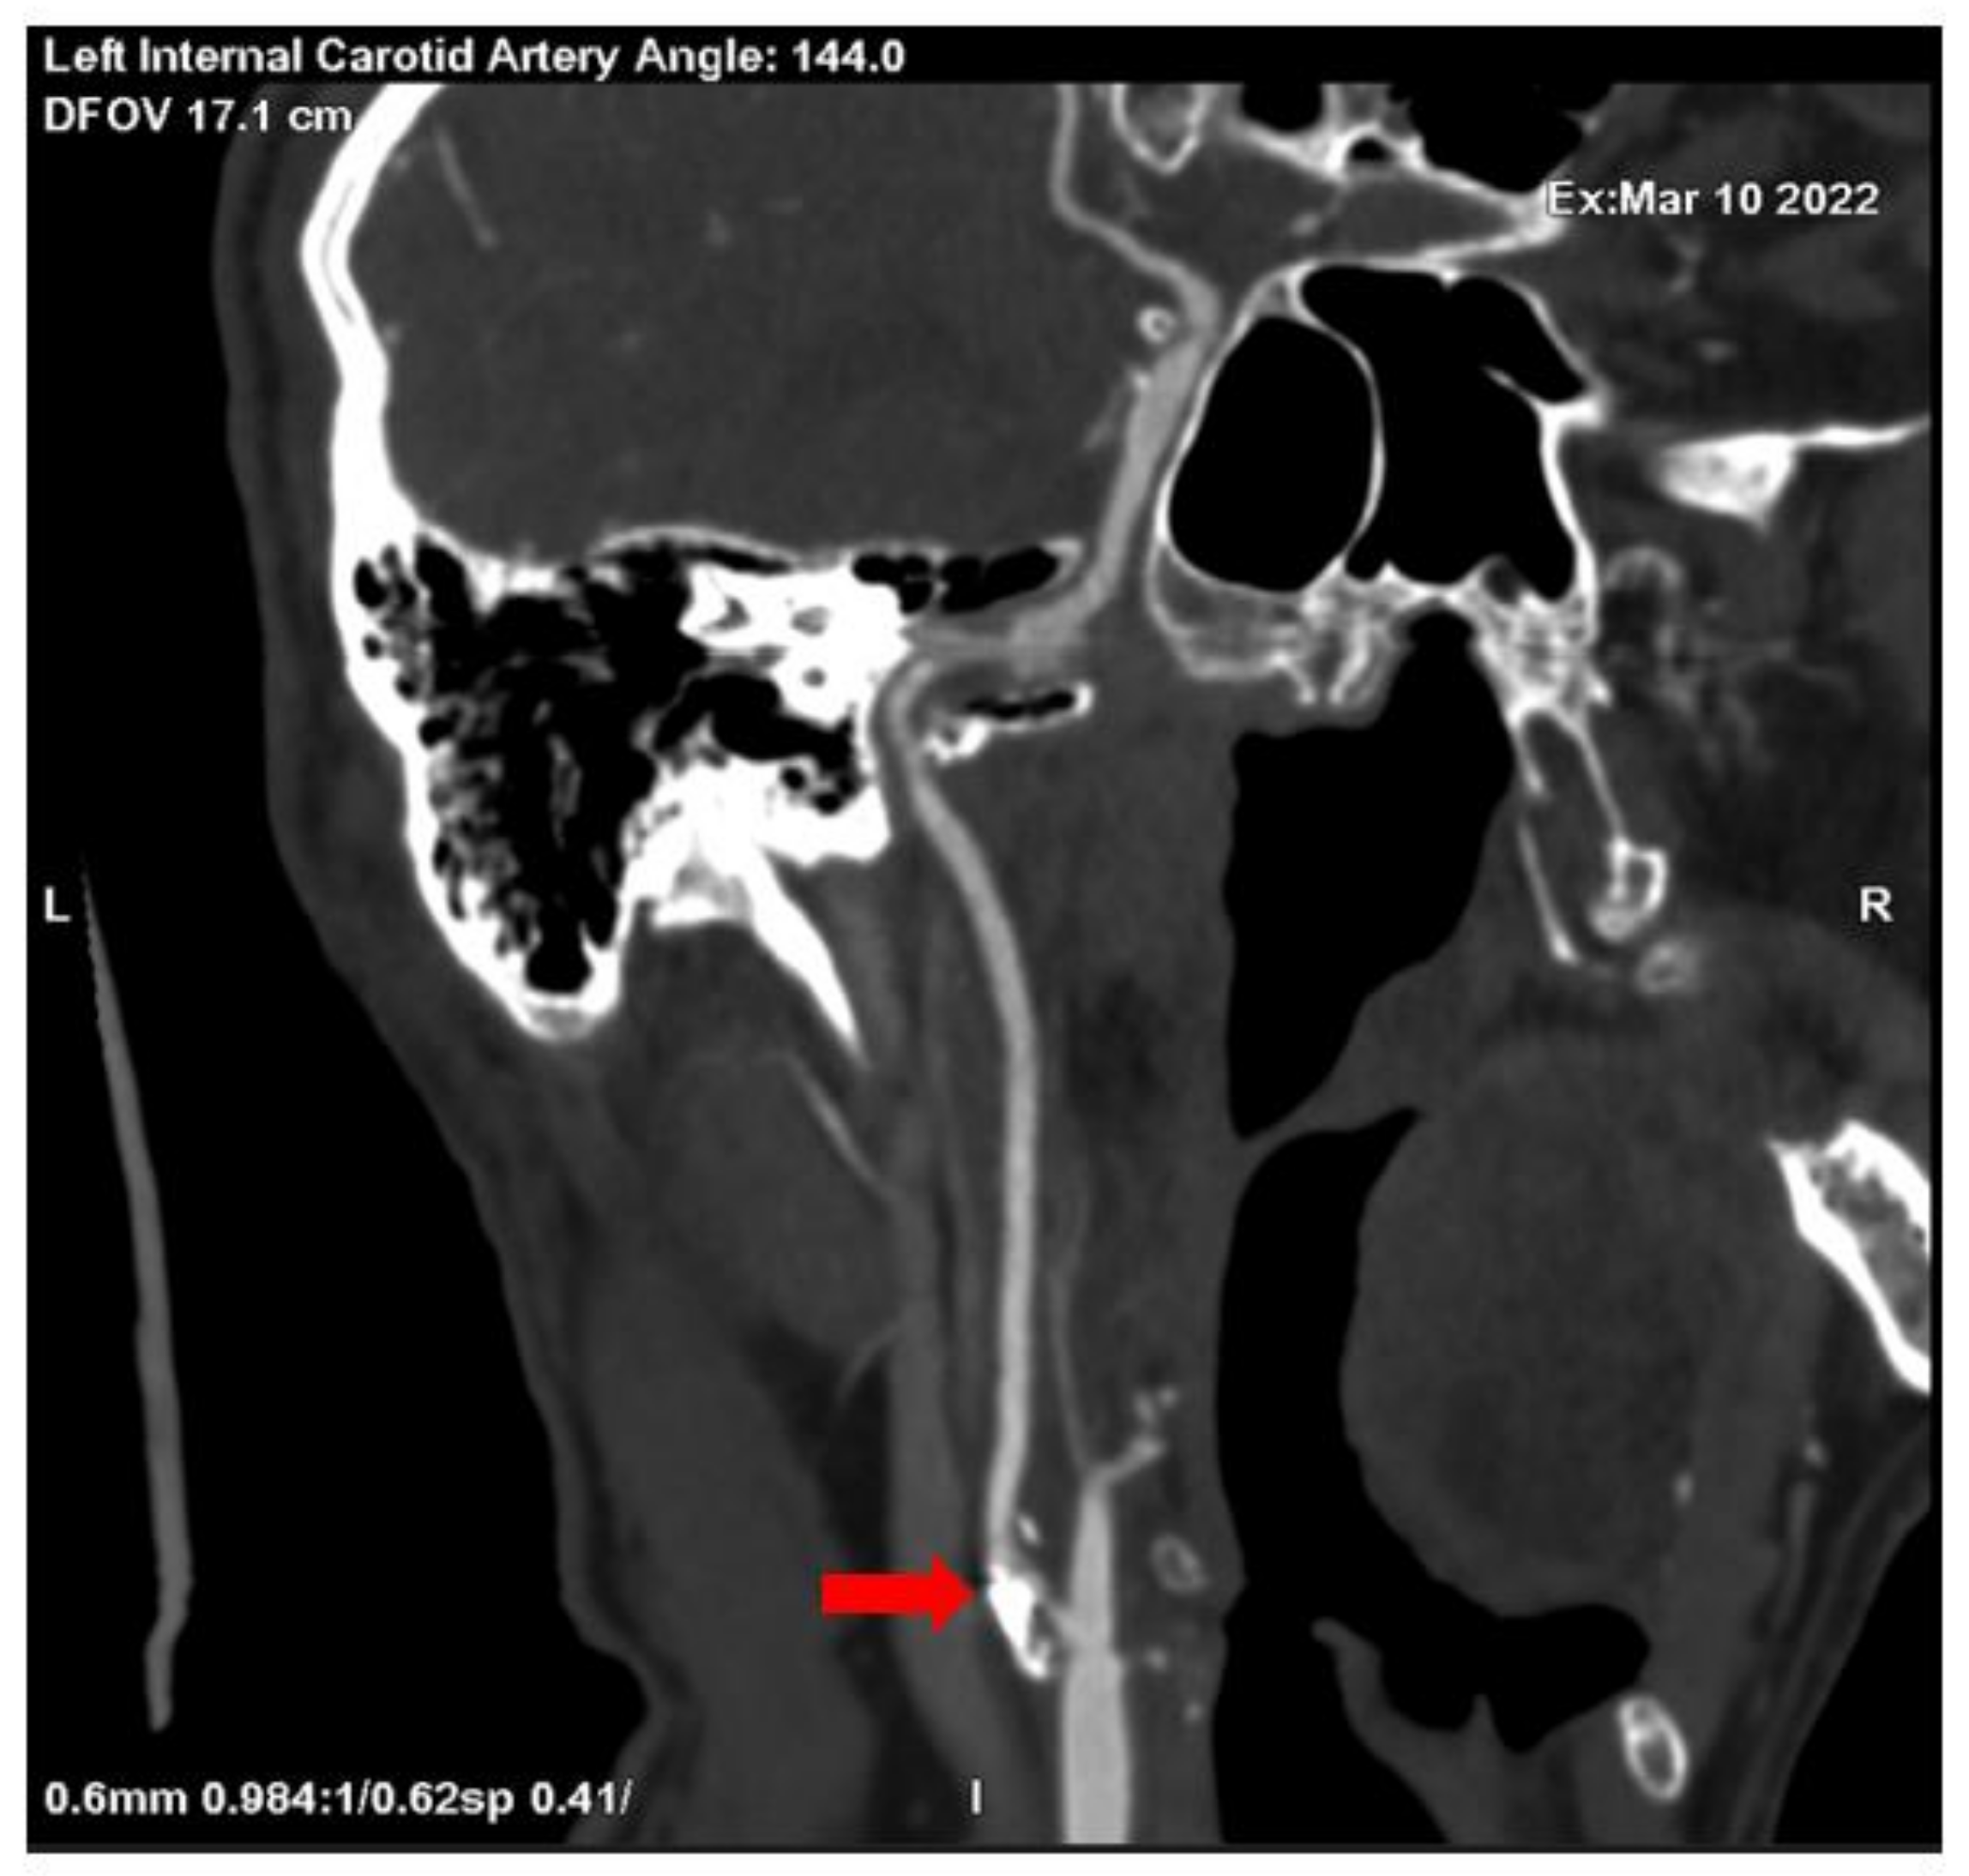

No significant changes were noted in the patient blood tests and patient urine analysis. When performed computed tomography angiography (CTA), subocclusion in the proximal segment of the left internal carotid artery was seen, as well as 30% stenosis in the proximal segment of the right internal carotid artery was observed (see Figure 1 and Figure 2).

Figure 1. Subocclusion in the proximal segment of the left internal carotid artery (CTA) (red array).